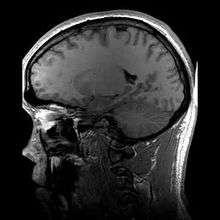

![]() Para-sagittal MRI of the head, with aliasing artifacts (nose and forehead appear at the back of the head) | |